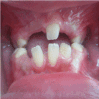

Intra-oral examination (Figure 4) revealed mixed dentition in her oral cavity. Teeth were

Figure 4. Oral cavity after improving oral hygiene and before  starting surgical exposure and orthodontic treatment.

The patient has poor oral hygiene, points of bleeding, but no pockets more than 3mm or tooth mobility.